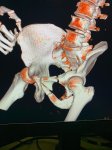

IMG20251208145138.jpg

Где пиздецома?